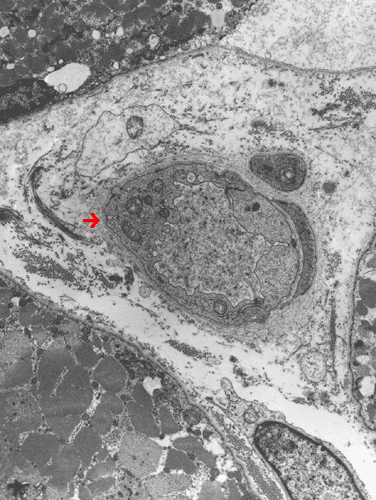

Note the endothelial cells (Ú) have enlarged cytoplasm.